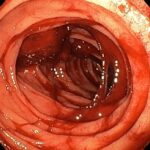

Desde el punto de vista diagnóstico, la lesión resulta difícil de detectar porque la alteración mucosa es extremadamente pequeña. Durante una endoscopia digestiva, el médico puede observar una mucosa aparentemente normal o solo una diminuta erosión. En muchos casos, la única pista visual es la presencia de un pequeño punto del que emerge sangre arterial activa o un vaso visible sin una úlcera circundante. La intermitencia del sangrado también puede dificultar su identificación, ya que el vaso puede no estar sangrando en el momento del examen.